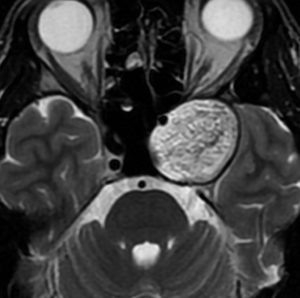

前頭蓋底類皮のう胞

蝶形骨平面から鞍結節上に発生するもので多いタイプです。左側のT2強調画像で内容物がまだらに見え,右側の拡散強調画像で高信号(白い)に見えるので診断確定です。内頸動脈や前大脳動脈や穿通枝などとの癒着が強いものが多いので剥離は難しく要注意です。ある程度の大きさを超えると経鼻内視鏡手術では摘出できません。この腫瘍は脳槽内にあるので,一回の手術でのう胞の壁も含めて全部摘出しなければなりません。そうしないと,手術後に内容物(皮脂と汗とケラチン)が髄液の中に産生されて漏れ出て,難治性の水頭症になります。